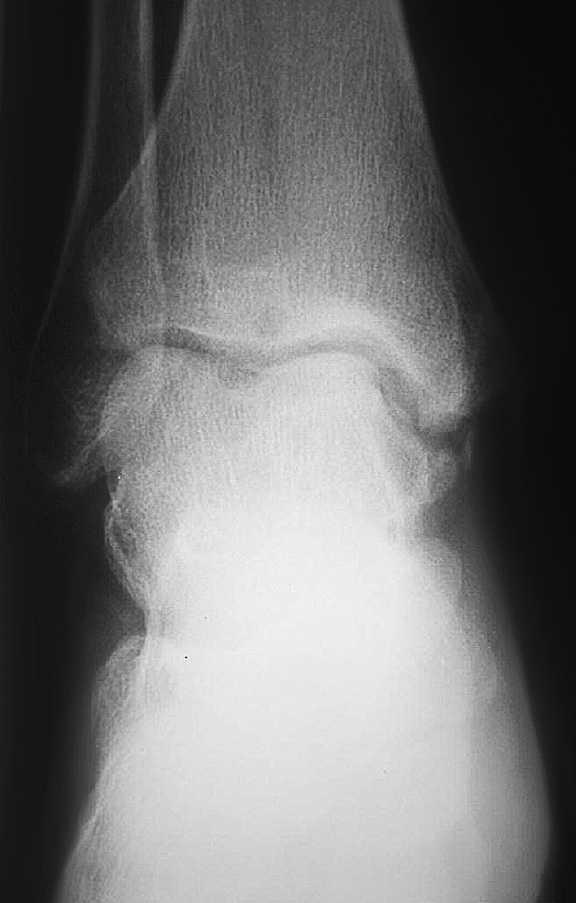

El seguimiento a la largo plazo de las fracturas del astrágalo identifica que la causa más común de los resultados pobres está asociada con la OA subastragalina, tibioastragalina y talonavicular, tanto en nuestra revisión, que alcanzó al 21% (8) de los casos (figs. 9 y 10), como en otros trabajos revisados15,17,19,22,23.

Fig. 9. --A) Fractura del cuerpo del astrágalo tipo B más rotura completa de los 3 ligamentos laterales del tobillo. B) Abordaje bilateral. Osteosíntesis. Sutura de ligamentos. Radiografía y tomografía computarizada a los 18 meses. Artrosis subastragalina y tibioastragalina.

Fig. 9. --a: Type B fracture of the astragalus with complete rupture of the 3 lateral ankle ligaments. b: Bilateral approach. Osteosynthesis. Ligament suture. Radiography and CT at 18 months. Sub-astragalar and tibio-astragalar arthrosis.

Fig.10. --Resultado a los 32 meses. 50° de BA. NAV del cuerpo y artrosis subastragalina y tibioastragalina

Fig.10. --Results at 32 months. BA 50º. Avascular necrosis of the astragalus and sub-astragalar and tibio-astragalar arthrosis.